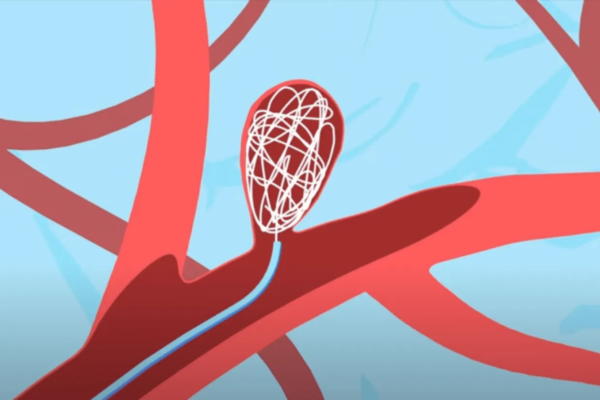

Seals aneurysms internally without stents, preserving normal blood flow.

Intrasaccular devices are placed directly inside the aneurysm sac to block blood flow at its origin. They are useful for select wide-neck aneurysms.

These devices seal the aneurysm internally without affecting the parent artery or surrounding brain circulation.